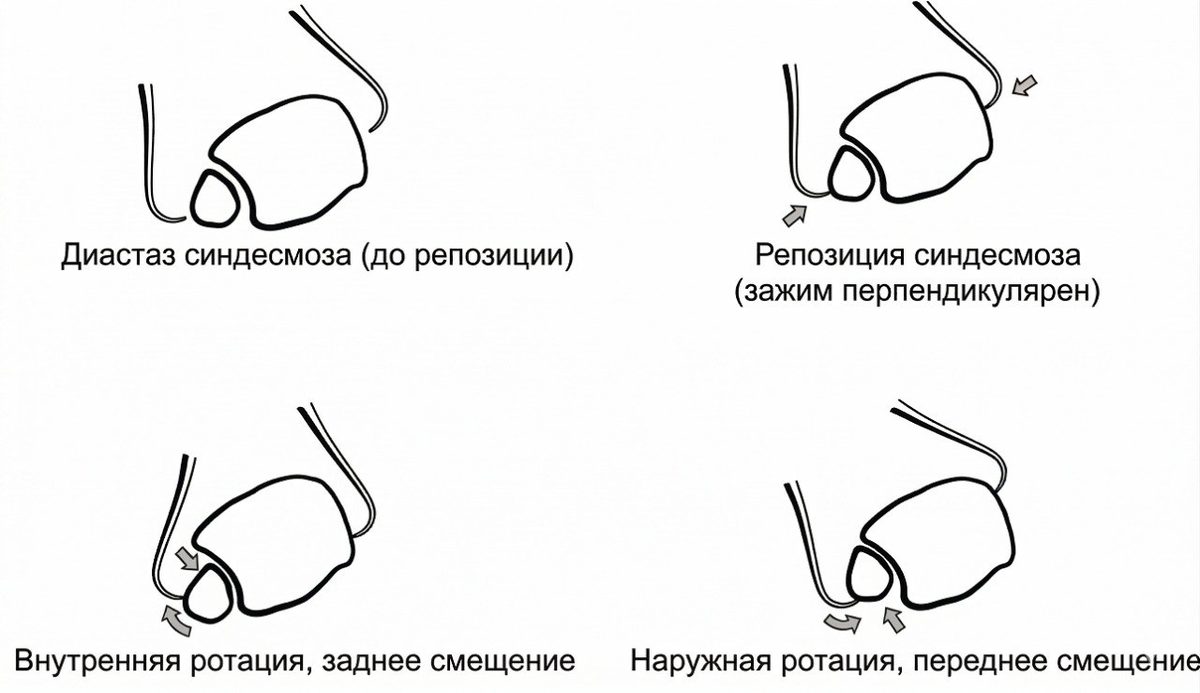

Повреждения синдесмоза традиционно классифицируют по трём степеням — аналогично латеральным растяжениям голеностопного сустава. I степень — умеренное растяжение, II степень — неполный разрыв, III степень — полный разрыв синдесмоза. Предложена также анатомическая классификация диастаза синдесмоза, разделяющая его на явный (frank) и скрытый (occult), с дальнейшим делением на коронарный, сагиттальный, ротационный и продольный типы.

Репозиция

Репозиция синдесмоза обычно выполняется с помощью репозиционных щипцов (bone clamp). Однако многочисленные исследования показали, что положение щипцов или винта может вызывать подвывих. Установка щипцов в нейтральном положении перпендикулярно синдесмозу сопровождается меньшим числом подвывихов по сравнению с косым положением. Прямая визуализация синдесмоза рекомендуется во всех случаях для минимизации риска подвывиха.

Рис. 20. Влияние положения щипцов на смещение малоберцовой кости при репозиции синдесмоза